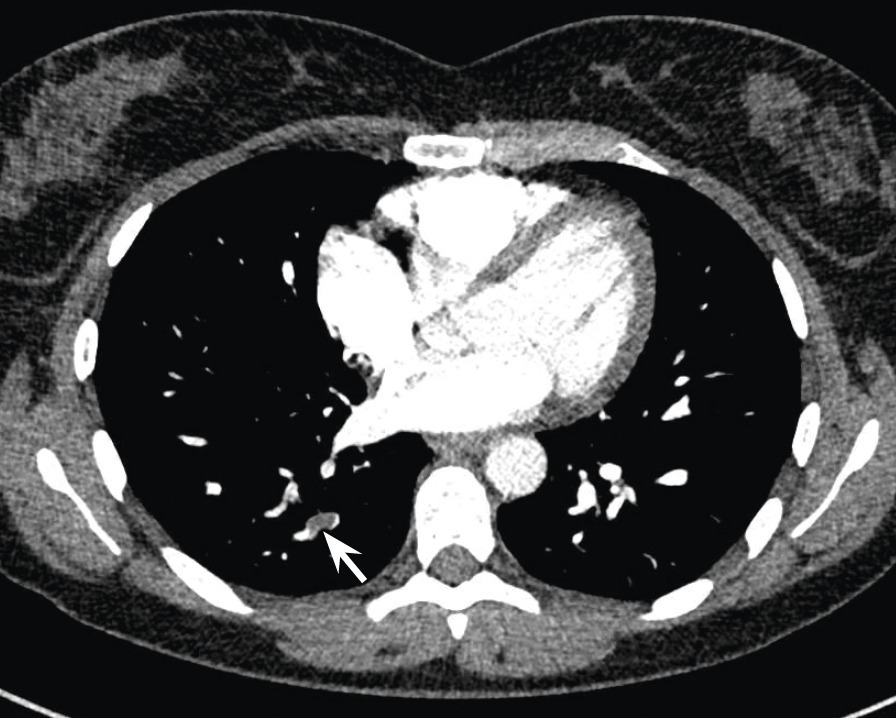

Une semaine après l’arrêt de l’aspirine, une dyspnée au moindre effort réapparaît. Les douleurs précordiales persistent mais sont moins intenses. Les D-dimères sont à 804 ng/mL, la CRP est à 11 mg/L et la troponine est négative. Un angioscanner pulmonaire réalisé en urgence montre une embolie pulmonaire sous-segmentaire postéro-basale droite, non compliquée.

Une lame d’épanchement péricardique est visible. La patiente est mise sous anticoagulant oral direct.